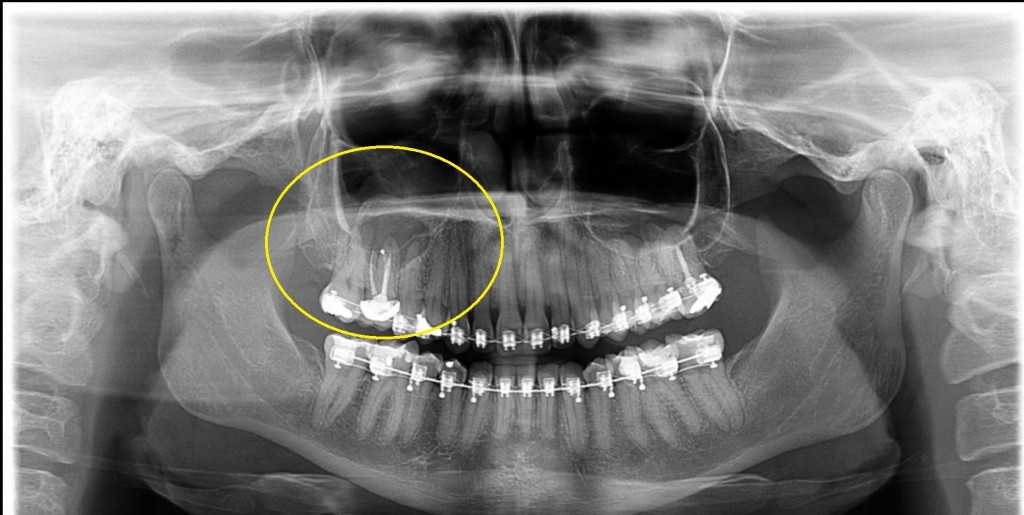

- Avaliação na ortodontia antes de colocar o aparelho;

Bem como a presença de supranumerários, agenesias, posições pré-eruptivas, transposições e posições ectópicas, dentes retidos, cistos foliculares, malformações coronárias dos germes dentários, direção axial dos dentes, anatomia radicular e dilacerações.

Também pode verificar a presença de cáries e as condições das restaurações existentes e a natureza de alguns desvios da linha mediana.

Por meio da panorâmica, é possível identificar doenças, sejam periodontais – relacionadas a perda de osso ao redor dos dentes -, cistos, tumores, inflamações e até mesmo sinusite.